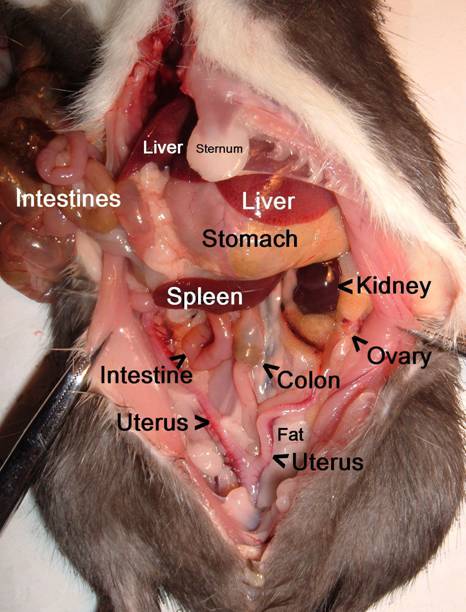

This picture shows the view when you first open the

abdomen. The large dark red organ at

the top is the liver. Just below it on the right is the stomach, with just the

tip of the dark red spleen visible at the far right, and on the left are the

small intestines. The large greenish structure is the cecum,

part of the large intestines. In rats who

haven’t been eating much, the cecum is usually

abnormally small.

This picture shows most of the deeper abdominal organs after

the intestines have been pulled up out of the way. The other kidney and ovary are on the

other side out of sight. The spleen has been pulled over to the

left of the picture but is usually between the stomach and kidney. The other organs not visible are the bladder

(at the base of the uterus), the pancreas (between the stomach and spleen), and

the cecum (lower right abdomen).